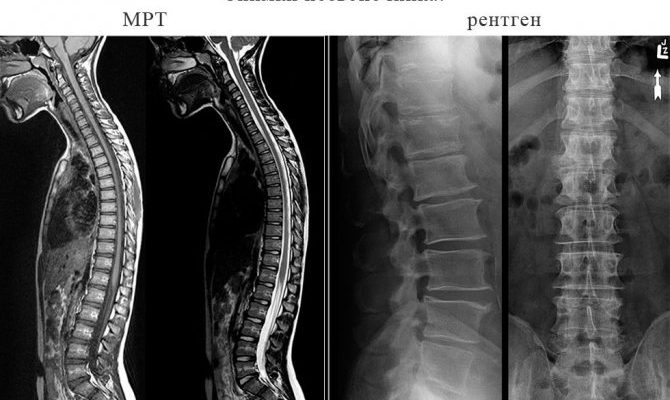

Клиническая медицина предлагает ряд диагностических методов, требуются рентген и магнитно-резонансная томография.

Рентгенография и МРТ: принципы выбора метода

Оба метода дают полную информацию, но отличаются принципом действия, разницей в способах достижения результата.

При попытке получить объективную оценку точности и информативности обоих типов исследований учитывается, что они не взаимозаменяемы и используются в разных случаях и ситуациях. Между тем различия в МРТ очевидны:

- Предоставляет подробные изображения позвоночника.

С помощью рентгена получить детальные изображения проблематично, так как функциональность устройства ограничена, хуже, чем при МРТ.

Оба вида диагностики отличаются высокой точностью и информативностью, тем не менее, характер предполагаемой патологии определяет выбор.

Магнитно-резонансная томография подходит для исследования мягких тканей, а рентгенологическое обследование врачи рекомендуют при нарушениях целостности костных структур и скелета.